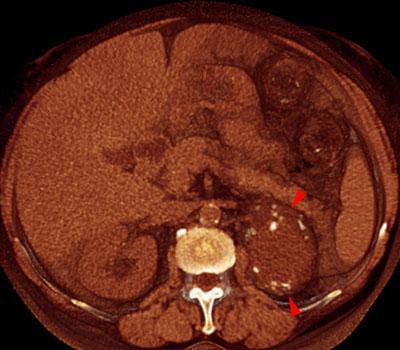

Quiste renal multitabicado e hipernefroma